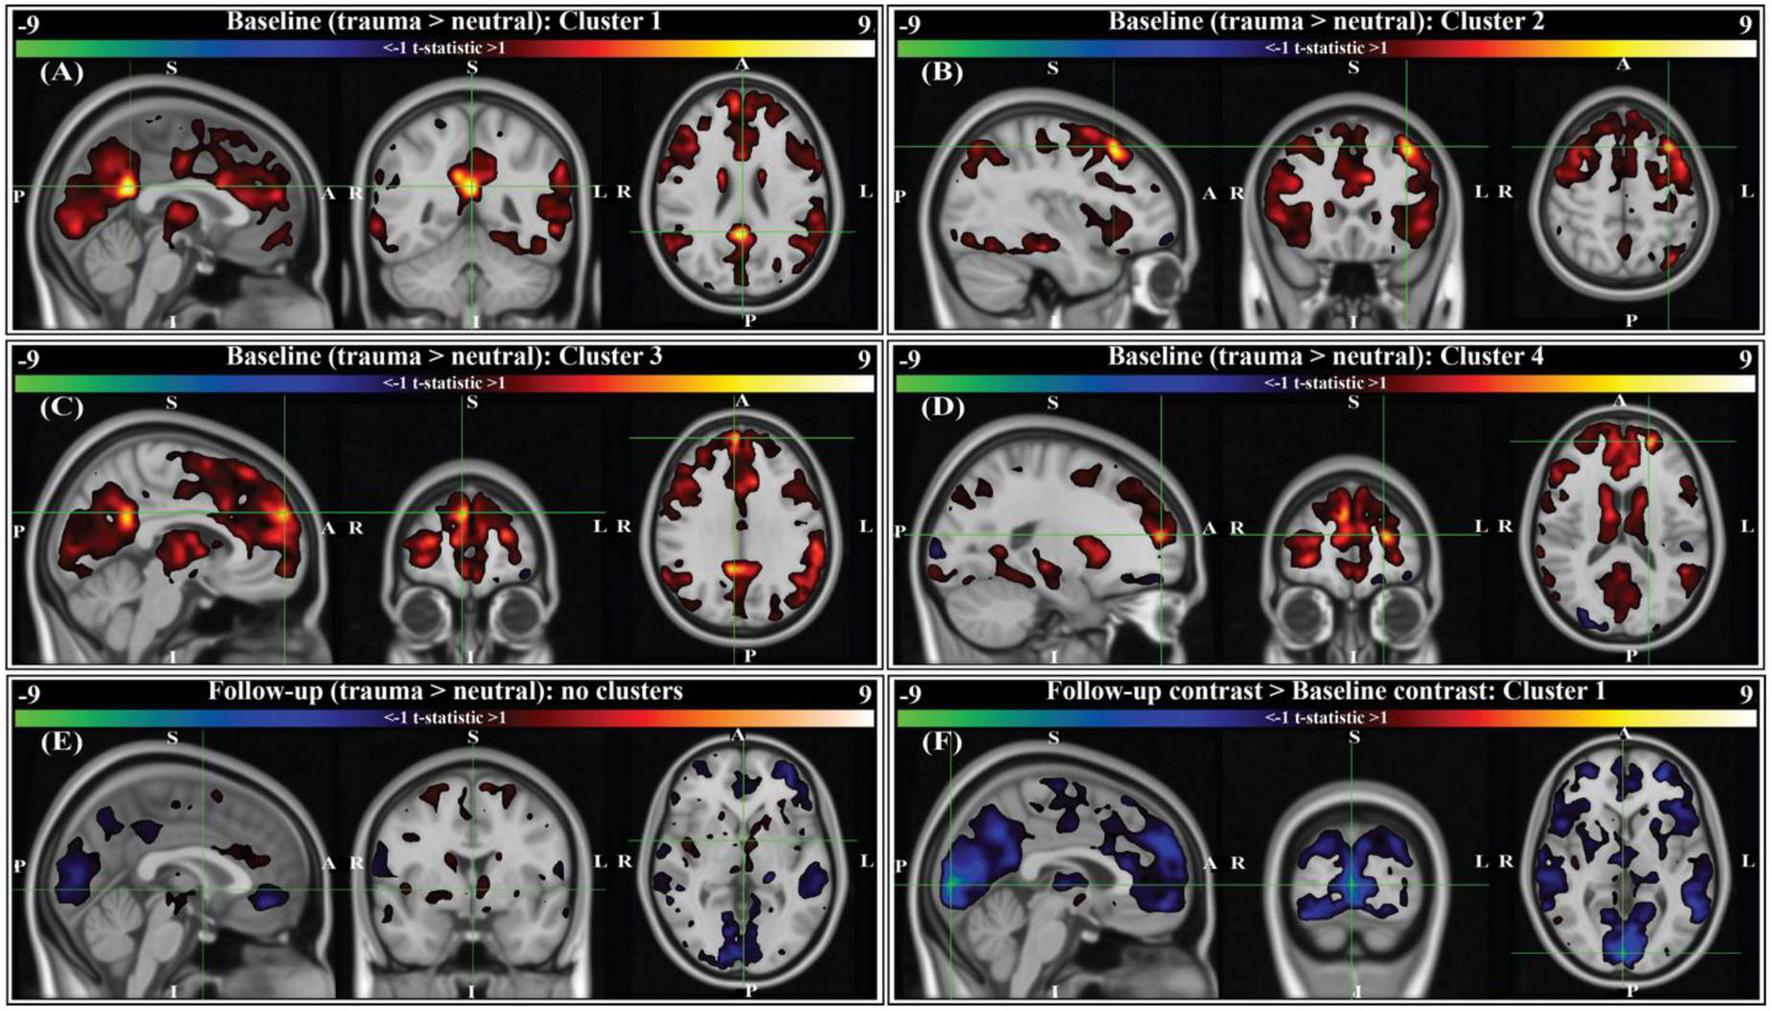

A script-driven autobiographical memory paradigm was used to assess brain activity during symptom provocation (66–68). We compared whole-brain, script-driven activations (trauma > neutral) at baseline and follow-up (Figure 4). Before therapy (baseline), there tended to be larger magnitude activation in response to the trauma script versus the neutral script, as evidenced by the generally positive t-statistics (Figures 4A–D). After correction using threshold free cluster enhancement (TFCE), there was significantly greater activation during the trauma scripts compared to the neutral scripts in four separate areas (see Figure 4 caption for details of each). After therapy, there were smaller magnitude differences between brain activity in response to the two scripts, with no significant clusters (Figure 4E). Finally, we assessed the differences in the contrast before and after therapy (follow-up > baseline). There was generally greater contrast between the trauma and neutral scripts at baseline compared to at follow-up, with one cluster in the bilateral cuneus and lingual gyrus demonstrating significance after correction using TFCE (Figure 4F).

Figure 4. Group-level activation contrasts for trauma versus neutral script listening tasks (N = 9). All panels show t-statistics for corresponding contrasts. Analyses were performed in 3 mm MNI standard space, however results here are interpolated into 1 mm MNI standard space and clipped to only show t-statistics greater than ± 1 for visualization purposes. Statistics reported below (voxels, volume, t-statistic, corrected p-value) were calculated from original 3 mm results. P-values were corrected using threshold-free cluster enhancement (TFCE; see section “2. Methods”). For panels (A–E), positive t-statistics indicate greater activation to trauma scripts compared to neutral. For panel (F), sign indicates the direction of change in trauma > neutral contrast from baseline (i.e., negative t-statistics indicate the contrast between trauma and neutral scripts was decreased at the two-month follow-up compared to baseline). Crosshairs are located on the center of gravity (c.o.g.) of significant clusters. (A) Cluster 1 for the baseline contrast is located primarily in the right and left isthmus cingulate, with some overlap into the right and left precuneus (c.o.g. MNI152 [0, –48, 24]; 6 voxels (162 mm3); c.o.g. t = 9.61, p(TFCE) = 0.0293). (B) Cluster 2 for the baseline contrast is located in the left caudal middle-frontal gyrus (c.o.g. MNI152 [-36, 21, 51]; 3 voxels (81 mm3); c.o.g. t = 9.01, p(TFCE) = 0.0234). (C) Cluster 3 for the baseline contrast is located in the right medial prefrontal cortex (c.o.g. MNI152 [6, 57, 30]; 2 voxels (54 mm3); c.o.g. t = 7.41, p(TFCE) = 0.0488). (D) Cluster 4 for the baseline contrast is located in the left rostral middle frontal gyrus (c.o.g. MNI152 [-21, 54, 15]; 1 voxel (27 mm3); c.o.g. t = 9.45, p(TFCE) = 0.0312). (E) There were no significant activation contrasts at the two-month follow-up (crosshairs shown at MNI152 [0, 0, 0]). (F) Comparing the group-level contrasts between time points (follow-up > baseline), there exists one significant cluster located primarily in the right and left cuneus, with some overlap into the right and left lingual gyrus (c.o.g. MNI152 [3, –90, 3]; 47 voxels (1,269 mm3); c.o.g t = –9.31, p(TFCE) = 0.0391).

We next sought to study brain response during autobiographical memory listening to draw additional conclusions about MDMA-AT’s effects in individuals with PTSD. Before therapy, participants had larger activation in four areas during an individualized trauma script listening task compared to neutral script listening: the right and left isthmus cingulate and precuneus, the left caudal middle frontal gyrus, the right medial prefrontal cortex, and the left rostral middle frontal gyrus (Figures 4A–D). These regions are broadly involved in self-processing operations (e.g., first-person perspective taking), episodic memory retrieval, visual-spatial imagery, auto-biographical memory recollection, and are included in or interact with the default mode network (44, 46, 49, 82–85). The retrosplenial cortex—located within the isthmus cingulate—is also found to be consistently activated by emotionally salient stimuli, and has been proposed to play a role in the interaction between emotion and memory (48). We conjecture that increased activation in these regions during traumatic compared to neutral audio listening (Figures 4A–D) could be related to an increased intensity of the recollection or re-experiencing of traumatic memories compared to neutral ones for patients before therapy. At 2-month follow-up to MDMA-AT, there was no significant difference in the trauma vs neutral script activation (Figure 4E). The longitudinal comparison of these two time points indicated that the contrast between trauma and neutral was larger at baseline, particularly in a significant cluster in the right and left cuneus/lingual gyrus (Figure 4F). Cuneus activity during autobiographical memory tasks often coincides with activity in the frontal regions highlighted by the baseline contrast, and has been found to correlate with memory recall accuracy (49, 83, 84). Cuneus activity is thought to enhance the visual imagery of autobiographical memory recollection (86), therefore decreased contrast in this area at follow-up suggests that intensity of visual imagery contrast between trauma and neutral memories may be decreased after MDMA-AT. Larger studies may allow more statistical power to identify additional longitudinal differences. Other longitudinal studies of individuals with PTSD have found that decreases in precuneus, isthmus cingulate, and middle frontal gyrus activation during symptom provocation is correlated with reductions in PTSD symptom severity (87, 88).